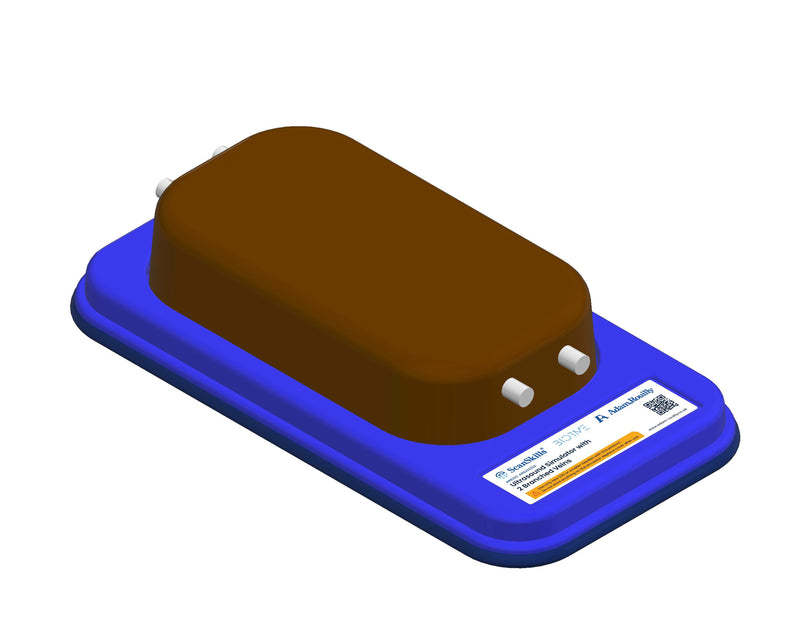

Thiết bị huấn luyện đơn giản, mạnh mẽ cho phép luyện tập lặp đi lặp lại kỹ thuật xâm nhập dưới hướng dẫn siêu âm một cách thực tế, giúp nâng cao thành thạo máy siêu âm, khéo léo sử dụng đầu dò và nhận biết cấu trúc giải phẫu. Tất cả chỉ với việc chuẩn bị và bảo trì tối thiểu.

Máy huấn luyện siêu âm BIOTME® mô phỏng mô người thật cả về cảm giác và đặc tính phản hồi sóng siêu âm. Vết kim sẽ biến mất sau vài ngày luyện tập, tăng cường tính chân thực và tiết kiệm chi phí.

Kích thước (Inch): 13 x 6.7 x 3.15